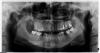

Корниенко Лариса Опубликовано 8 июня, 2010 Автор Поделиться Опубликовано 8 июня, 2010 (изменено) Уважаемые господа специалисты! Очень надеюсь на вашу помощь! Обратилась к врачу по поводу протезирования 46 и 47 зубов. Получила ответ, что нужны анкерные штифты в оба зуба. В 47-й штифт поставлен, а в 46-м распломбировали канал и сначала поставили что-то на неделю, но зуб стал болеть, затем поставили метапекс. Прошло 2 месяца. Зуб иногда слабенько ноет, но врачи (4 врача) рекомендуют его удалять ввиду отторжения зуба, говорят, что лечить- это пустая трата денег, все равно придется удалять а воспаление перекинется на 47-й, таким образом, потеряю и его. Вопросы: 1.Возможно ли сохранение зуба и с помощью каких лечебных мероприятий? 2.Если удалять, то мне светит съемный протез? Снимок панорамный сделан год назад, а прицельный свежий. Заранее благодарна. Извиняюсь, не получилось отправить все сразу! 23 ни при чем, ошибочно! Изменено 8 июня, 2010 пользователем Корниенко Лариса Ссылка на комментарий

Корниенко Лариса Опубликовано 9 июня, 2010 Автор Поделиться Опубликовано 9 июня, 2010 Уважаемый Мартовский! Большое Вам спасибо! Считаю себя пациентом «со стажем» и прекрасно знаю, что даже за немалые деньги не всегда получаешь квалифицированную помощь. Если Вас не затруднит, то можно еще вопрос? Сначала предыстория. Над 6-й справа надулась десна, зуб не болел, гноя снаружи не было, прошло все без лечения (теперь понимаю свою ошибку). Через месяц начался сильнейший гайморит с той же стороны. После обращения к ЛОРам заключение: обострение хр. гайморита, мицетома (инор. тело-пломбир.материал?)верхнечелюстной пазухи. Операция. Мицетома удалена, пазуха вычещена, куча антибиотиков и постоянная субфебрильная t между курсами антибиотиков, сильная слабость и боль всей правой половины головы. Не буду сильно утомлять своей «поэмой», короче, далее следовали еще 2 реоперации (у очень хороших докторов) и штук 50 проколов (каждый раз с гнойным отделяемым) . Проблема сохранялась. Компьютер. томограф. ситуацию не прояснила (аппарат, специалист- кто виноват?). И только «посидев» в инете составила свою схему лечения: первым делом посетила стоматолога и пролечила 6-ки сверху (справа при лечении корней были зловонные выделения), 7-ка справа удалена (кусок инструмента в верхушке корня, выходящий в сторону гайморовой пазухи). С гайморитом не распрощалась, но t нет и состояние нормальное, хотя гной в пазухе продолжает скапливаться. Почему? ЛОРы ответа не знают. Все это длится 2 года. Вопрос: может быть без удаления 6-ки результата не достичь? Хотя консультировалась у многих стоматологов и хирургов, говорят, что удалять не надо (по ортопантограмме), этот зуб ни при чем. Зуб пролечен хорошо (без штифта с каким-то стекловолокном). Если удалю- «светит» съемный протез (лет-то мне еще не много). Вроде корни не выходят в пазуху, просто близко- так мне сказали. Данная ортопантограмма сделана до лечения год назад. Если хватило терпения дочитать- спасибо за выдержку! Хотелось бы узнать мнение специалиста: оставлять ли мне этот злополучный зуб или ставить коронку? Понимаю, что без КТ сложно ответить на мой вопрос. Ссылка на комментарий